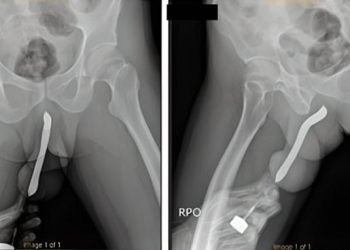

Man left in excruciating pain after shoving toothbrush into his manhood during s3x A man was left in excruciating ...